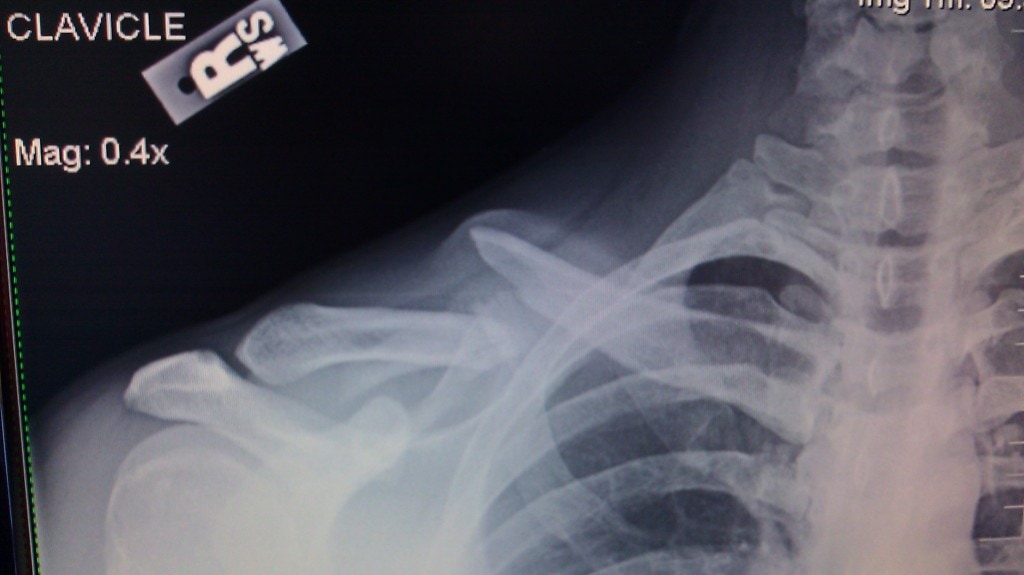

He reached into his shirt and felt the bone sticking out on his right shoulder. He skied over to one of the ski officials and requested medical help. He rode the sled straight into the ER at the base of the mountain.

After seeing three different specialists, he’s decided to have surgery tomorrow morning (3-1-12). He is going to the University of Chicago where they will put a plate in place to hold the 5 broken pieces of his clavicle together.

This was not his only option, but seems like the best way to go for him. He wears a heavy backpack daily for work (HVAC Technician) and hopes to be able to do so again without discomfort.